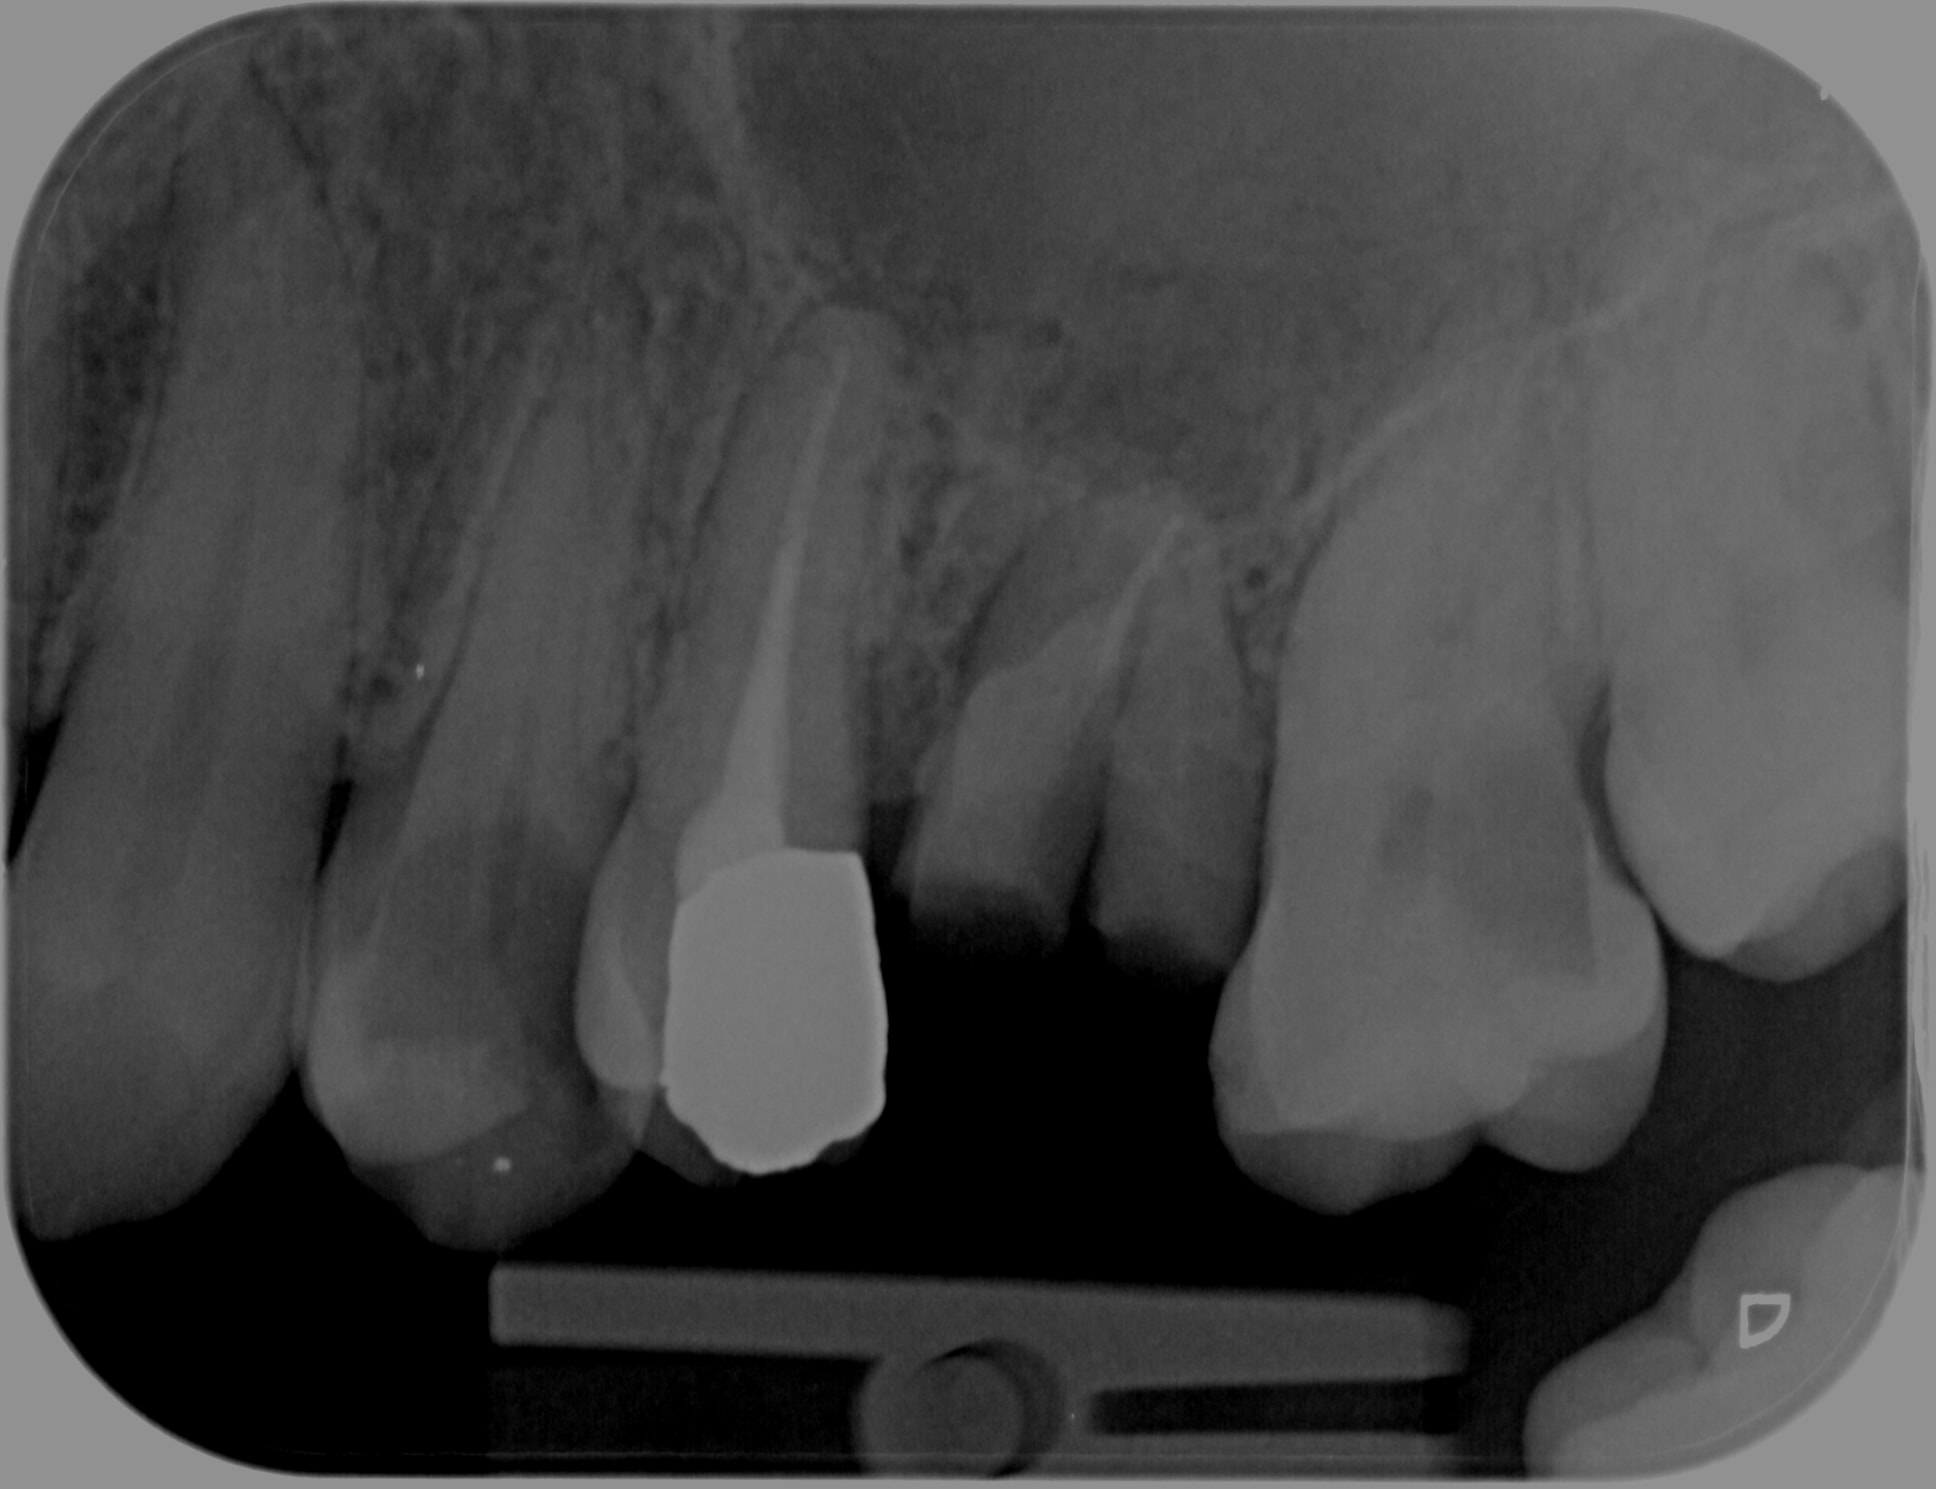

Tu vois celui là a consulté parce que sa ceram posée il y a 4 mois s'est cassée ( curieux d'ailleurs pour une full zircone d'un esthétique saisissant A4 au lieu de B2 ). Il a oublié de lui soigner la 25 par contre. C'est ballot. -)

J'en ai chié à la virer mais j'ai pas pu résister à l'appel du spr 57. Pour une fois que l'endo n'était pas à reprendre. . -)